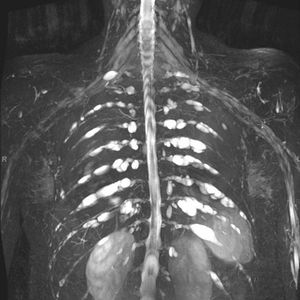

Neurofibromatosis

Thick MIP of 3D SPACE.